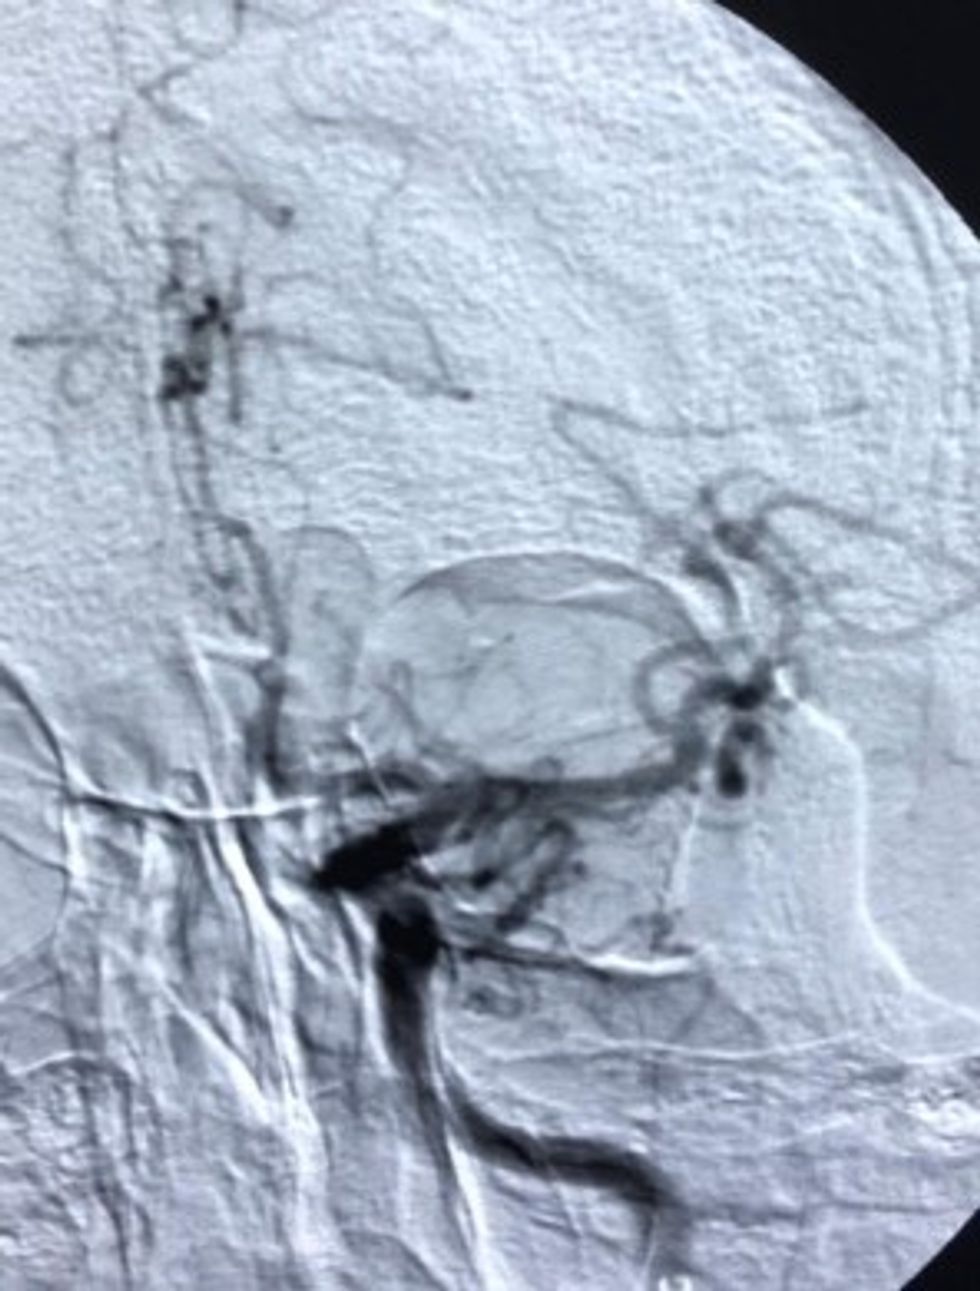

Për herë të parë në kuadër të Qendrës Klinike Universitare të Kosovës, Klinika e Radiologjisë, ka realizuar heqjen e gjakut të ngjizur në arterien e trurit në mënyrë mekanike (trombektomia mekanike e M2 segmentit të arteries cerebri media majtas) me metodë radiologjike neurointervente minimale invazive.

"Procedura u krye pa komplikime, tek pacienti mashkull i moshës 62 vjeç, i cili kishte dorën e palëvizshme dhe këmbën e djathtë të dobësuar, pas procedurës i është kthyer menjëherë lëvizshmëria e dorës së djathtë.

Poashtu, të folurit e humbur në tërësi, kurse pas 12 orëve nga kryerja e procedurës, pacienti ka filluar të artikuloj zë dhe lëvizë lirshëm edhe me këmbë.", thuhet në njoftimin e QKUK-së.

:Brenda 3 apo 4 orëve pas sulmit në tru, procedurën e kanë realizuar ekipi i radiologëve, Dr. Bujar Gjikolli, Dr. Arben Kutllovci, përkrahur nga radiologët kujdestar Dr. Agron Arifi, Dr. Ilir Bejta, me referimin e neurologëve kujdestar Dr. Rushit Jashari, Dr. Valbona Spanca e Dr. Milaim Krasniqi, me asistimin e teknikëve të radiologjisë Shekfi Bytyqi, Ariana Neziri.